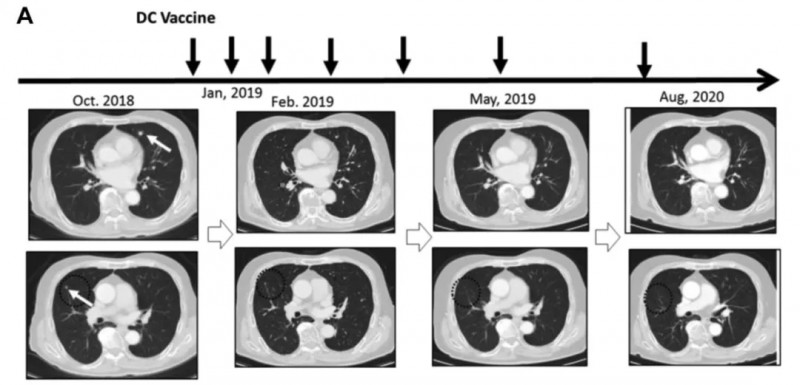

《抗癌研究》杂志曾报道一项“新抗原肽脉冲DC疫苗单药治疗晚期实体肿瘤”的临床研究,多例患者治疗反应良好且无严重不良事件,其中一例肾细胞癌肺转移患者疗效尤为显著。

该患者2018年7月术后2个月出现多发肺转移,因肺静脉血栓无法使用靶向药,遂于2019年1月起接受新抗原肽脉冲DC疫苗治疗。

结果显示:接种3剂后获部分缓解(PR);接种6剂后接近完全缓解(CR),肿瘤基本消失;2020年8月复查CT,证实其维持持久完全缓解(CR)(详见下图)。

▲图源“Anticancer research”,版权归原作者所有,如无意中侵犯了知识产权,请联系我们删除